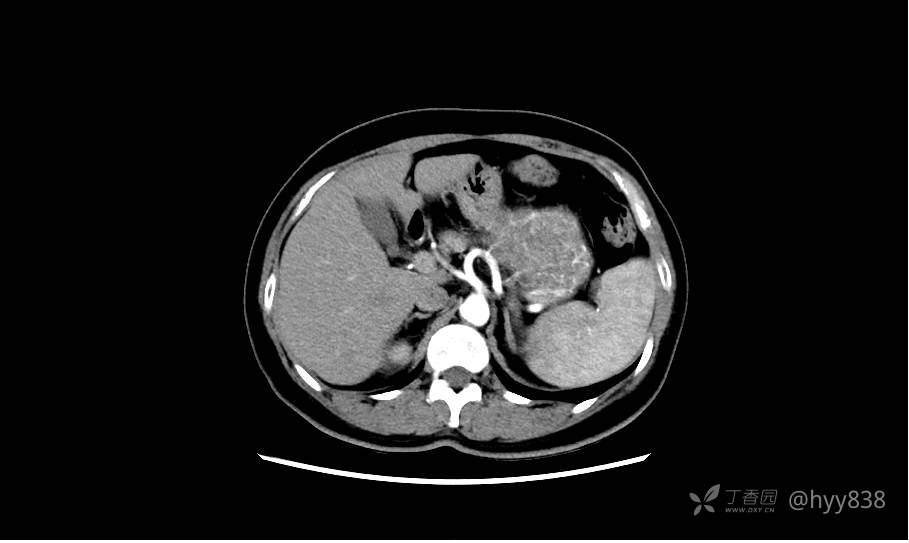

胰腺增强动脉期